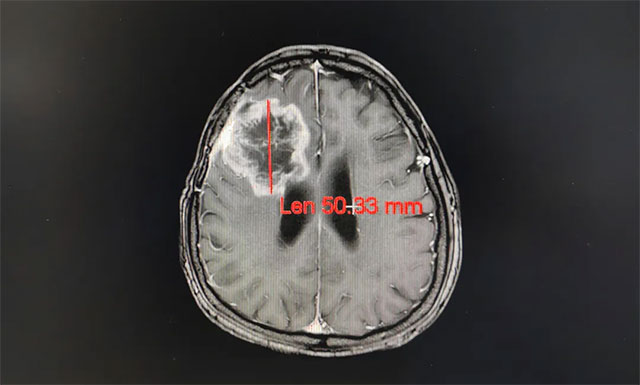

完善其各项检查,王晓东主任根据姚女士的临床资料、病理诊断和影像结果,确定患者满足放疗条件,并制定了完善周密的放疗计划。之后患者进行了一个疗程(30次)的放射治疗,放疗期间未见明显不良反应,经过放射治疗,姚女士的病灶由原来的61.52mm缩小到50.33mm;其头痛、恶心症状明显改善,大小便也恢复正常,走路不稳的症状也得到了缓解。

▲ 经过放射治疗患者病灶变小,其症状明显改善